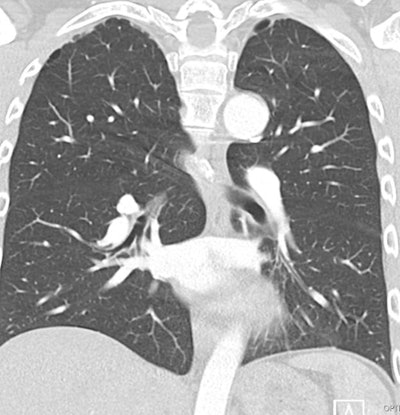

Pulmonary diseases. One of the more characteristic pulmonary imaging findings is the so-called "tulip bulb" configuration of the upper lungs. This refers to a subtle widening of the upper lobe apices with concave tapering inferiorly on frontal chest radiographs or coronal CT images. It is thought to be related to upper lobe emphysematous changes or apical pleural blebs. These structural abnormalities, along with an increased incidence of spontaneous pneumothorax, are important to recognize, particularly in younger patients presenting with acute chest pain and no trauma history. In rare cases, restrictive lung disease may result from severe scoliosis or pectus excavatum, contributing to impaired pulmonary mechanics.

30-year-old man with biapical blebs and a history of Marfan syndrome. CR image shows the classic tulip bulb shape of Marfan syndrome.